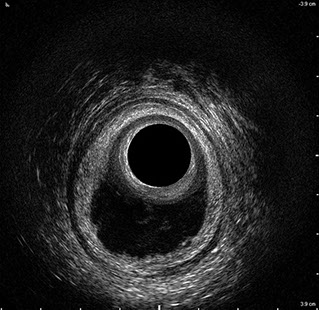

Proctal dispone di apparecchiatura per ecografia endoanale 3D con sonda rotante.

Sezione Longitudinale 3D con Tramite Fistoloso Intersfinterico Basso Anteriore Semplice